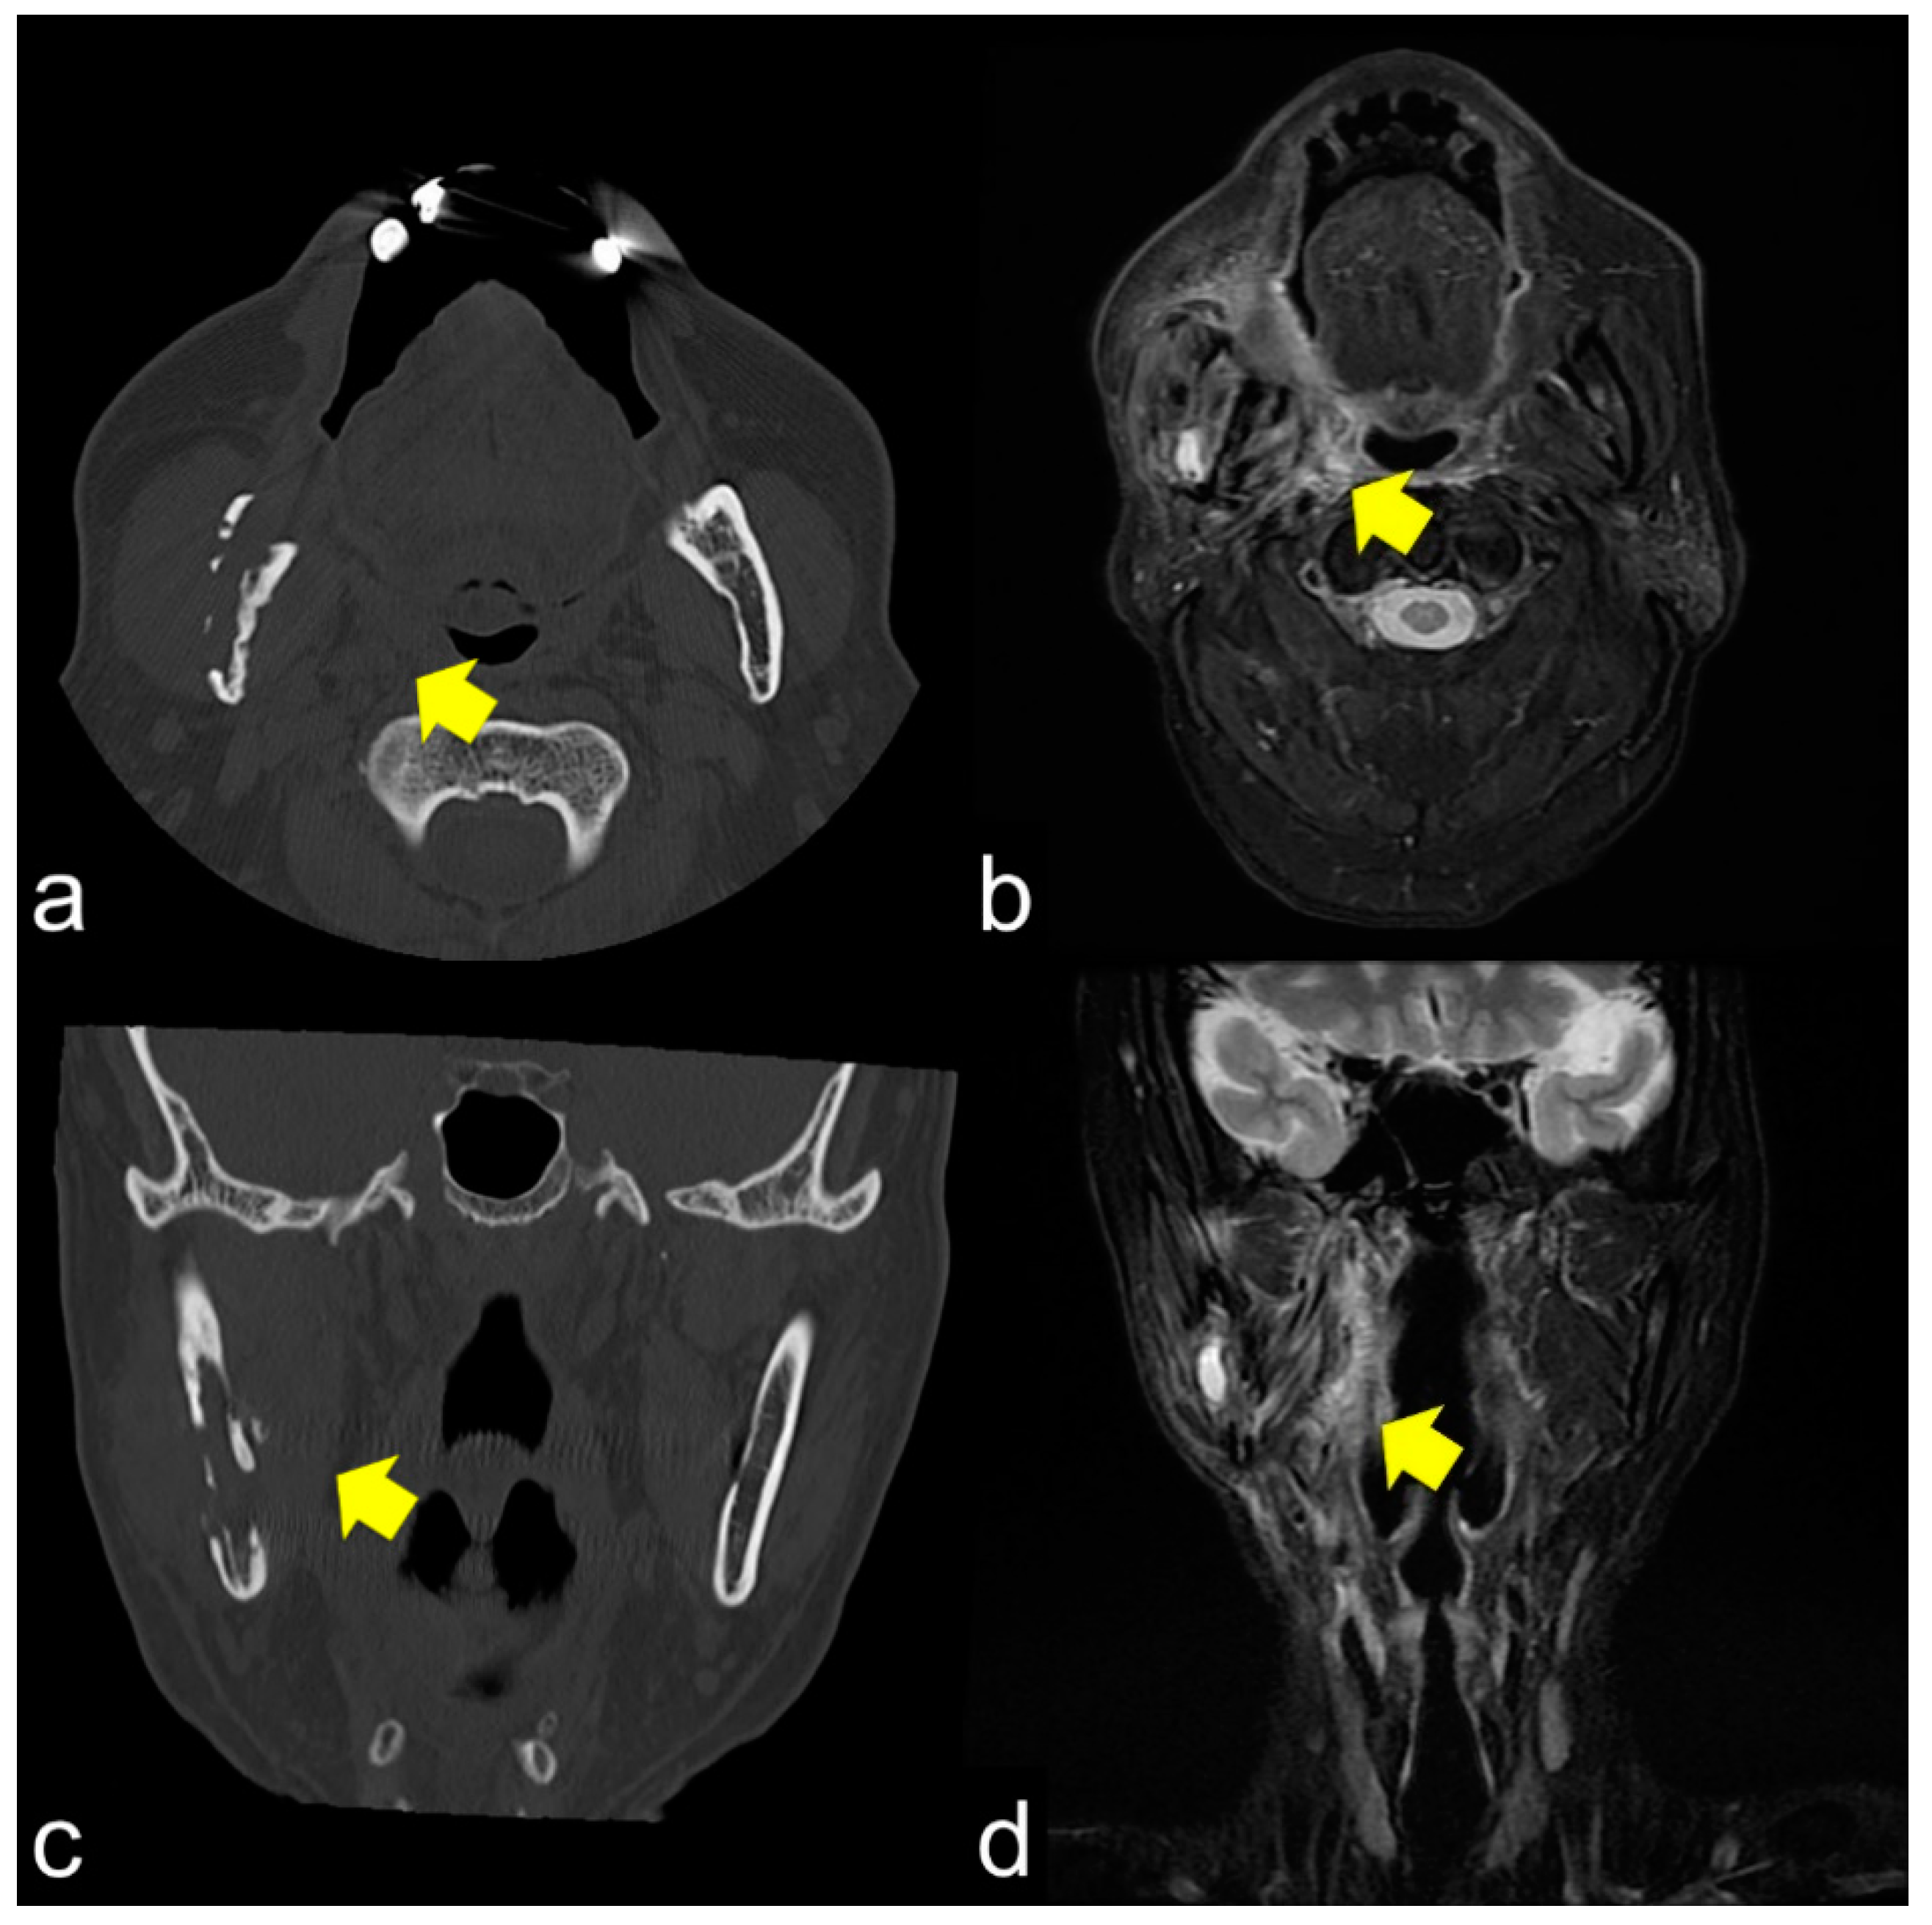

PET/CT findings of ORN reflect the disease course and indicate the point of clinical remission in patients with chronic osteomyelitis [40,41,42]. PET is effective in detecting tumor recurrence. Bone scintigraphy has been used to diagnose ORN; however, there is no quantitative index to evaluate ORN activity. In this study, we obtained information on the existence of ORN; however, the detailed situation of ORN could not be evaluated because of the low level of specificity [13]. Since the development of bone SPECT can aid in various quantitative SUV analyses, SPECT/CT is a promising modality for the analysis of ORN [42].

The same lesions captured by PET/CT and SPECT are shown in Figure 4a,b, respectively. PET/CT is useful for differentiating tumor recurrence. On the other hand, SPECT provides useful information regarding bone activity. PET/CT appeared to represent glucose metabolism, including the bone marrow, which was hyper-metabolized, and SPECT appeared to represent areas of increased bone metabolism; PET reflected inflammatory soft tissue and/or tumor recurrence and SPECT showed inflammatory and/or neoplastic bone tissue. PET/CT and SPECT are sensitive indicators of altered osteoblastic activity, but local disturbances in vascular perfusion, clearance rate, permeability, and chemical binding also affect imaging [13]. It is occasionally difficult to differentiate soft tissue uptake from bone uptake in patients with known cellulitis and possible underlying osteomyelitis. In terms of tumor recurrence, PET/CT and SPECT is useful but not definitive. Incisional biopsy is required for the final diagnosis.

Figure 4.

PET/CT (a) and single-photon emission computed tomography (SPECT) (b) images of the same lesion. PET/CT clearly shows soft tissue inflammation around the ORN area, while SPECT specifically shows bone inflammation. This comparison would help detect tumor recurrence.